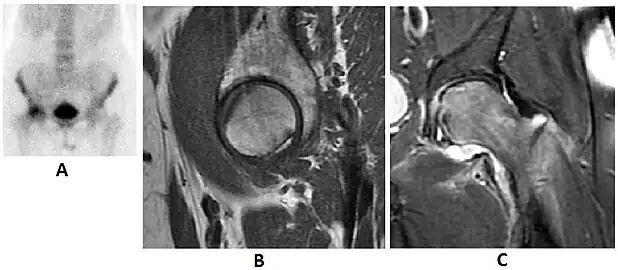

Synovial chondromatosis can be confidently diagnosed by X-ray when calcified cartilaginous chondromas are seen. However, other synovial proliferative processes, such as pigmented villonodular synovitis, require MRI for accurate diagnosis, although noncalcified synovitis can be suspected in radiographs by indirect signs, such as soft tissue swelling and/or erosions in the femoral head, femoral neck, or acetabulum (Figure 7).[1]

Figure 7:

-

Axial CT image of pigmented villonodular synovitis eroding the posterior cortex of the femoral neck.[1] -

Sagittal T2* gradient echo image showing a posterior soft tissue mass with hypointense areas secondary to hemosiderin deposition.[1] -

X-ray of synovial chondromatosis.[1] -

CT of synovial chondromatosis.[1]

In synovial proliferative disorders, MRI demonstrates synovial hypertrophy. In the case of PVNS, characteristic foci of low signal intensity related to hemosiderin deposition are better seen on gradient echo T2* images (Figure 7). In the case of synovial osteochondromatosis, the synovial hypertrophy is accompanied by intermediate signal cartilaginous loose bodies and/or low signal calcified loose bodies.[1]